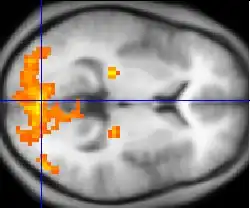

Changes in brain activity are closely coupled with changes in blood flow in those areas, and knowing this has proved useful in mapping brain functions in humans. The measurement of haemodynamic response, in a clinical setting, can be used to create images of the brain in which especially active and inactive regions are shown as distinct from one another. This can be a useful tool in diagnosing neural disease or in pre-surgical planning. Functional MRI and PET scan are the most common techniques that use haemodynamic response to map brain function. Physicians use these imaging techniques to examine the anatomy of the brain, to determine which specific parts of the brain are handling certain high order functions, to assess the effects of degenerative diseases, and even to plan surgical treatments of the brain.

Functional magnetic resonance imaging (fMRI), is the medical imaging technique used to measure the haemodynamic response of the brain in relation to the neural activities.[12] It is one of the most commonly used devices to measure brain functions and is relatively inexpensive to perform in a clinical setting. The onset of neural activity leads to a systematic series of physiological changes in the local network of blood vessels that include changes in the cerebral blood volume per unit of brain tissue (CBV), changes in the rate of cerebral blood flow, and changes in the concentration of oxyhemoglobin and deoxyhemoglobin. There are different fMRI techniques that can pick up a functional signal corresponding to changes in each of the previously mentioned components of the haemodynamic response. The most common functional imaging signal is the blood-oxygen-level dependent signal (BOLD), which primarily corresponds to the concentration of deoxyhemoglobin.[13] The BOLD effect is based on the fact that when neuronal activity is increased in one part of the brain, there is also an increased amount of cerebral blood flow to that area which is the basis of haemodynamic response. This increase in blood flow produces an increase in the ratio of oxygenated hemoglobin relative to deoxygenated hemoglobin in that specific area. The difference in magnetic properties of oxygenated and deoxygenated hemoglobin is what allows fMRI imaging to produce an effective map of which neurons are active and which are not. In short, deoxygenated hemoglobin is paramagnetic while oxygenated hemoglobin is diamagnetic. Diamagnetic blood (oxyhemoglobin) interferes with the magnetic resonance (MR) signal less and this leads to an improved MR signal in that area of increased neuronal activity. However, Paramagnetic blood (deoxyhemoglobin) makes the local magnetic field inhomogenous. This has the effect of dephasing the signal emitted in this domain, causing destructive interference in the observed MR signal. Therefore, greater amounts of deoxyhemoglobin lead to less signal. Neuronal activity ultimately leads to an increase in local MR signaling corresponding to a decrease in the concentration of deoxyhemoglobin.[14]

If fMRI can be used to detect the regular flow of blood in a healthy brain, it can also be used to detect the problems with a brain that has undergone degenerative diseases. Functional MRI, using haemodynamic response, can help assess the effects of stroke and other degenerative diseases such as Alzheimer's disease on brain function. Another way fMRI could be used is in the planning of surgery of the brain. Surgeons can use fMRI to detect blood flow of the most active areas of the brain and the areas involved in critical functions like thought, speech, movement, etc. In this way, brain procedures are less dangerous because there is a brain mapping that shows which areas are vital to a person's life. Haemodynamic response is vital to fMRI and clinical use because through the study of blood flow we are able to examine the anatomy of the brain and effectively plan out procedures of the brain and link together the causes of degenerative brain disease.[15]